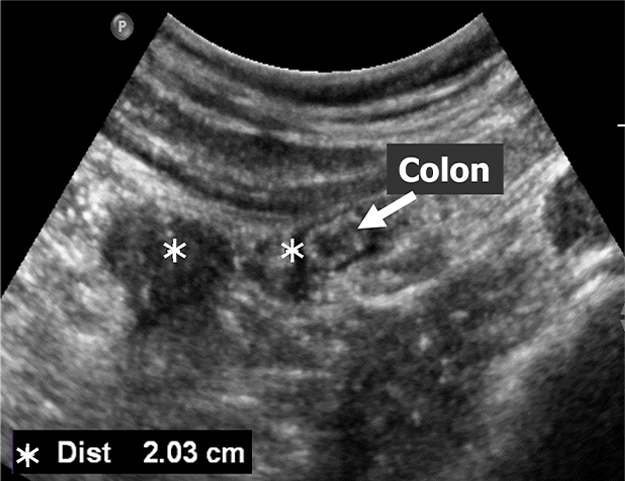

In conventional US-guided ablation (Figure 4), the physician typically places a few landmarks on in-plane 2D US images to estimate the required ablation zone. Although a 5–10 mm safety margin is commonly applied in clinical practice to reduce the risk of residual tumours, this approach may still fail to ensure complete tumour coverage. Moreover, to maintain procedural safety, the physician must carefully review multiple US views to avoid ablating critical structures such as the colon (Figure 5).

Assessment 2

Figure 5. Tumour coverage assessment with surrounding structures.